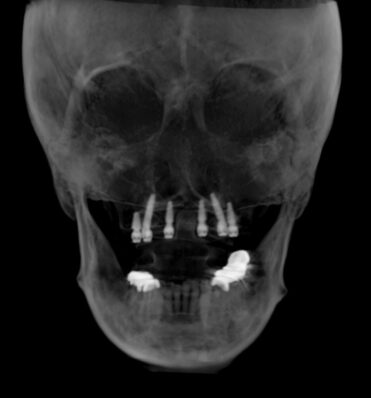

ストローマン主催のライブオペコースを渋谷医院にて行いました。

渋谷医院では少人数制のライブオペを行っており、参加者の先生方はオペからラボでのプロビジョナルの制作、そして患者さんへのセットまでの流れをすべて見ることができます。

今回も順調に10時半のオペスタートから12時頃までのプロビジョナルのセットの一連の流れを経験していただきました。

今回は上顎の歯がボロボロで長年苦労されていた症例でした。

手術寸前に前歯が取れてしまいとてもお困りでしたので、プロビジョナルの装着後とても喜ばれていました。